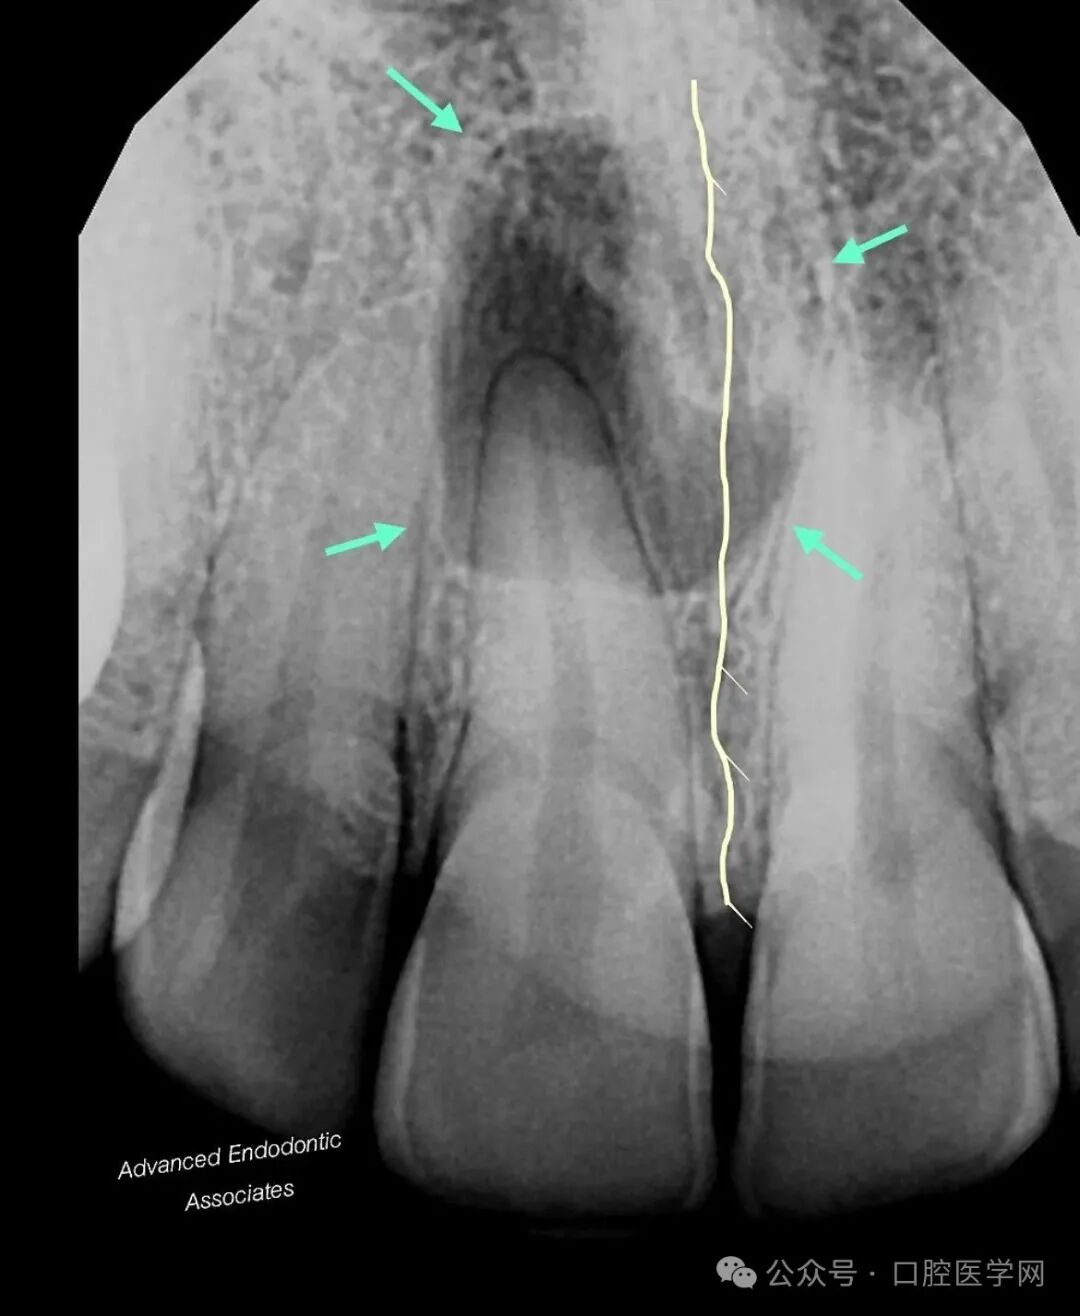

在分析二维放射影像时,两个关键特征强烈提示病变的本质可能为非牙源性:

1. 完整的牙周膜(PDL):放射片显示病变区域内牙周膜结构完整。需特别注意,若在病变区域内可清晰追踪到牙周膜影像,表明该病变与牙根表面关联的可能性极低。

2. 跨越中线的特征:透射区可见跨越中线,这一表现不符合牙源性病变的典型特征。牙源性病变(LEOs)极少出现跨越中线的情况,仅在严重或广泛性感染病例中可能发生。

结合上述影像学特征及CBCT评估,我们明确诊断为“切牙管囊肿”。患者随后被转诊至口腔颌面外科医生处,进行进一步随访及治疗。